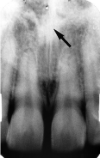

37. What is the anatomical structure indicated by arrow in this radiograph?

38. What is showing by arrow?

39. What is showing by the arrow?